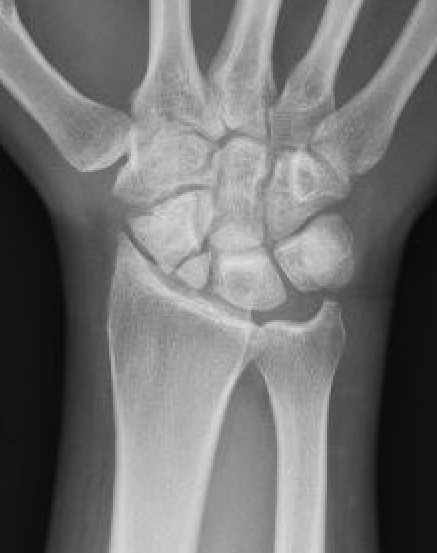

Rheumatoid wrist

SLAC wrist

SNAC wrist

Kienbock's disease